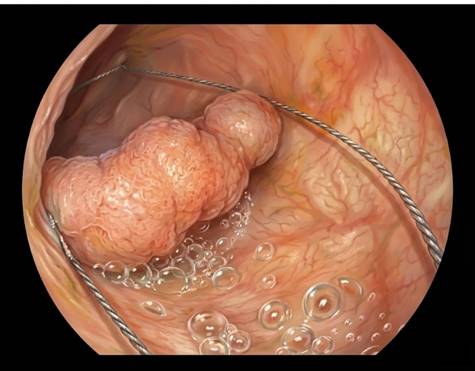

Resección mucosa endoscópica (RME)

La RME, también llamada mucosectomía, es la técnica estándar para retirar muchos pólipos grandes. Se inyecta líquido bajo el pólipo para levantarlo, se coloca un lazo metálico y se corta el tejido con corriente eléctrica. En una recidiva, la cicatriz está más rígida y la lesión puede “no levantar” bien, lo que complica el procedimiento. Aun así, las recurrencias tras una primera RME de pólipos grandes clásicamente rondaban el 10–25 %. Con técnicas complementarias más recientes, como la ablación de los márgenes con punta de asa, esta cifra ha bajado hasta un 5%. En todo caso, esas recurrencias con frecuencia son pequeñas y se solucionan con una segunda RME en manos experimentadas. La calidad técnica, esto es, cómo se inyecta, se corta y se tratan los bordes, pesa casi tanto como los factores relacionados con el pólipo.

Antes de ir a quirófano, suele valer la pena plantear si una unidad experta puede intentar una segunda RME sobre la recidiva. En algunos casos se combinan maniobras adicionales, como la avulsión con pinza para arrancar pequeños restos.